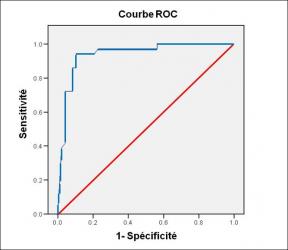

Performance diagnostique de l’interféron gamma dans l’identification de l’origine tuberculeuse des pleurésies exsudatives